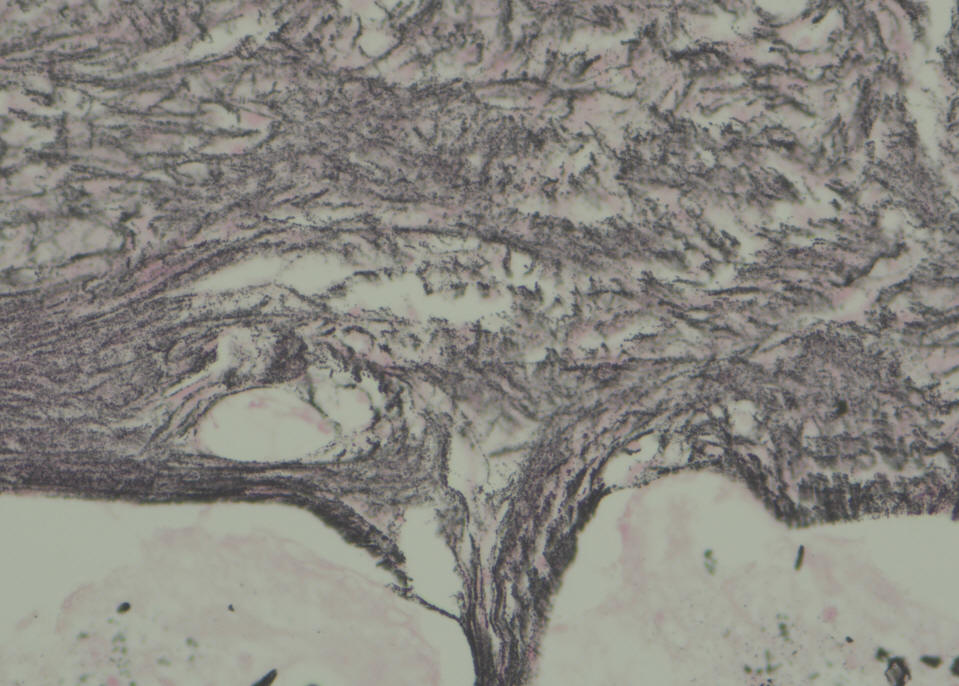

SONOCA 300

Sections show a circumscribed tumor composed of spindle cells displaying prominent nuclear palisading and Vercoy bodies. This lesion exhibits peripheral tongues extending into the brain cortical tissue. There is no evidence of mitotic activity, nuclear anaplasia or necrosis. Tumor shows heavy interstitial reticulin deposition and reacted positively to S-100 and Vimentin. Tumor did not react to GFAP and EMA. Proliferative index was estimated at 2%, but not exceed 3% in any area. There is no evidence of malignancy. Conclusion: Intracerbral schwannoma. ( Prof. Yahya F. Dajani Consultant pathologist. 29-January-2022.